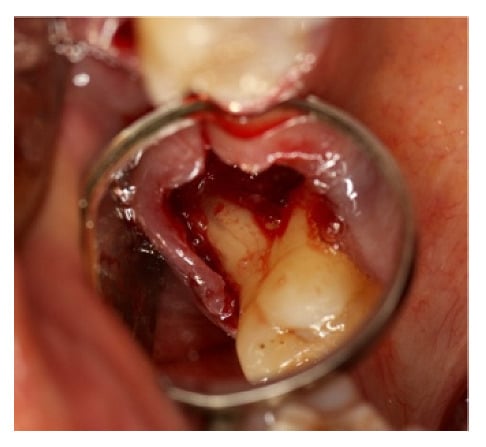

In this case of chronic periodontal abscess between teeth 1.7 and 1.6, there was an important buccal and palatal periodontal pocket of 9 mm with a large resorption of the interdental bone septum. It was decided to extract the tooth 1.7 because of its poor prognosis (Figure 19a,b).

(a) Periapical radiograph of teeth 1.7, 1.6, 1.5; (b) important probing periodontal mesial root of 1.7.

A large amount of infected granulation tissue was present in furcation space, between the distal-buccal and palatal root (Figure 20).

Furcation lesion between the distal buccal root and the palatal tooth 1.6 after 1.7 extraction.

The alveolar cavity and roots were curetted and cleaned with a solution of physiological water and hydrogen peroxide 1:1 and collagen sponges, completely wetted by the blood from the surgical site, were applied and followed by the protective positioning of a shaped foil.

After three months, the foil was removed (Figure 21a,b) and the roots surface previously exposed, appeared covered by bone.

(a) Removal of sutures after 3 weeks; (b) extensive healing tissue is observed which has completely covered the previously exposed roots.